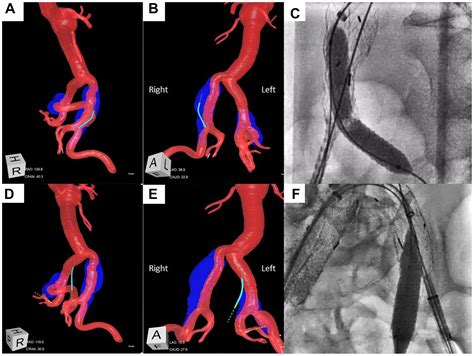

• Endovascular Repair: This minimally invasive procedure involves inserting a stent-graft through a small incision in the groin and guiding it to the site of the aneurysm. The stent-graft reinforces the weakened artery wall and prevents rupture.

• iliac artery aneurysm repair

Endovascular repair of bilateral common iliac artery aneurysms using ...

2781×2092